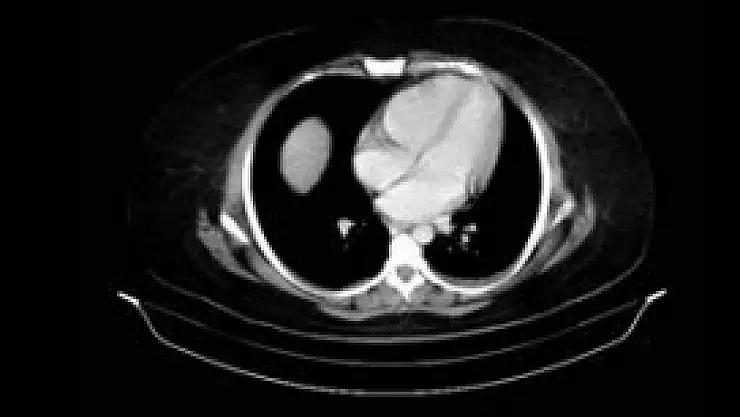

Daha önce safra kesesindeki taş nedeniyle safra kesesi alınan 27 yaşındaki Ayşe Bulut, 3 aydır çektiği karın ağrısı şikayeti üzerine Özel Medicana Konya Hastanesine başvurdu. Prof. Dr. Faruk Aksoy tarafından muayene edilen hastanın yapılan tetkiklerde, safra kesesindeki taşların tıkanması neticesinde pankreas bezinde 10 santimetre büyüklüğünde kist oluştuğu belirlendi. Tıbbi tedaviye rağmen kistin büyüyerek mide çıkışında daralmaya neden olması nedeniyle bulantı, kusma ve zayıflama görüldüğü için hasta ameliyata alındı.

Prof. Dr. Aksoy, ameliyatla kistin boşaltılıp mide çıkışında daralmanın giderildiğini söyledi. Prof. Dr. Aksoy, “Aynı zamanda kistin duvarı ile midenin arka duvarı birleştirilerek pankreas psöobkisti’nin tedavisi gerçekleştirildi. Kistin büyüme ihtimali yoktu. Büyüyebileceği son noktadaydı. Ameliyat olmasaydı hasta karnında pankreas apsesi oluşurdu. Patlaması durumunda hayati tehlikesi olabilirdi” dedi.